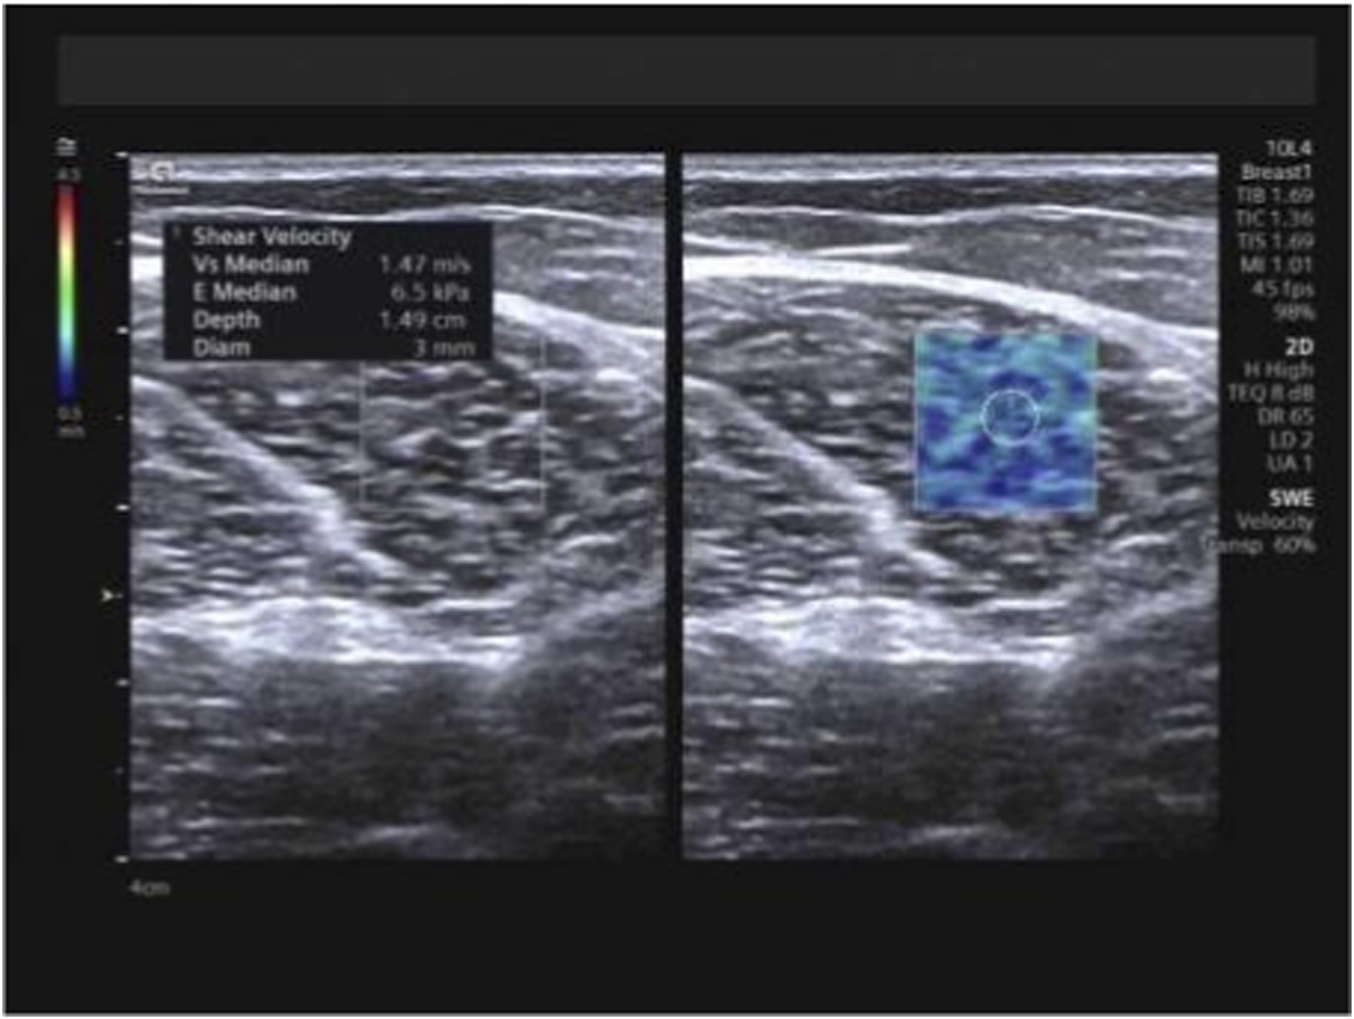

At the identical locations used for muscle thickness measurement, SWE examinations were performed pre-intervention and subsequently after 1 month, 3 months, and 6 months of training, utilizing the aforementioned measurement positions and techniques. Following conventional ultrasound imaging, the system was switched to SWE dual-display mode. The transducer was maintained perpendicular to the skin surface and carefully aligned parallel to the tendon/muscle fibers. The sample box was adjusted, and the image was frozen once stabilized. Using the system’s integrated measurement tools, Emean and SWVmean were measured, with the mean value derived from three consecutive measurements for each parameter (Figures 4–6).

FIGURE 4

Measurement of Emean and SWVmean values for the trapezius. Note: Emean denotes mean Young’s modulus; SWVmean denotes mean shear wave velocity.

Measurement of Emean and SWVmean values for the long head of the biceps femoris. Note: Emean denotes mean Young’s modulus; SWVmean denotes mean shear wave velocity.

FIGURE 6